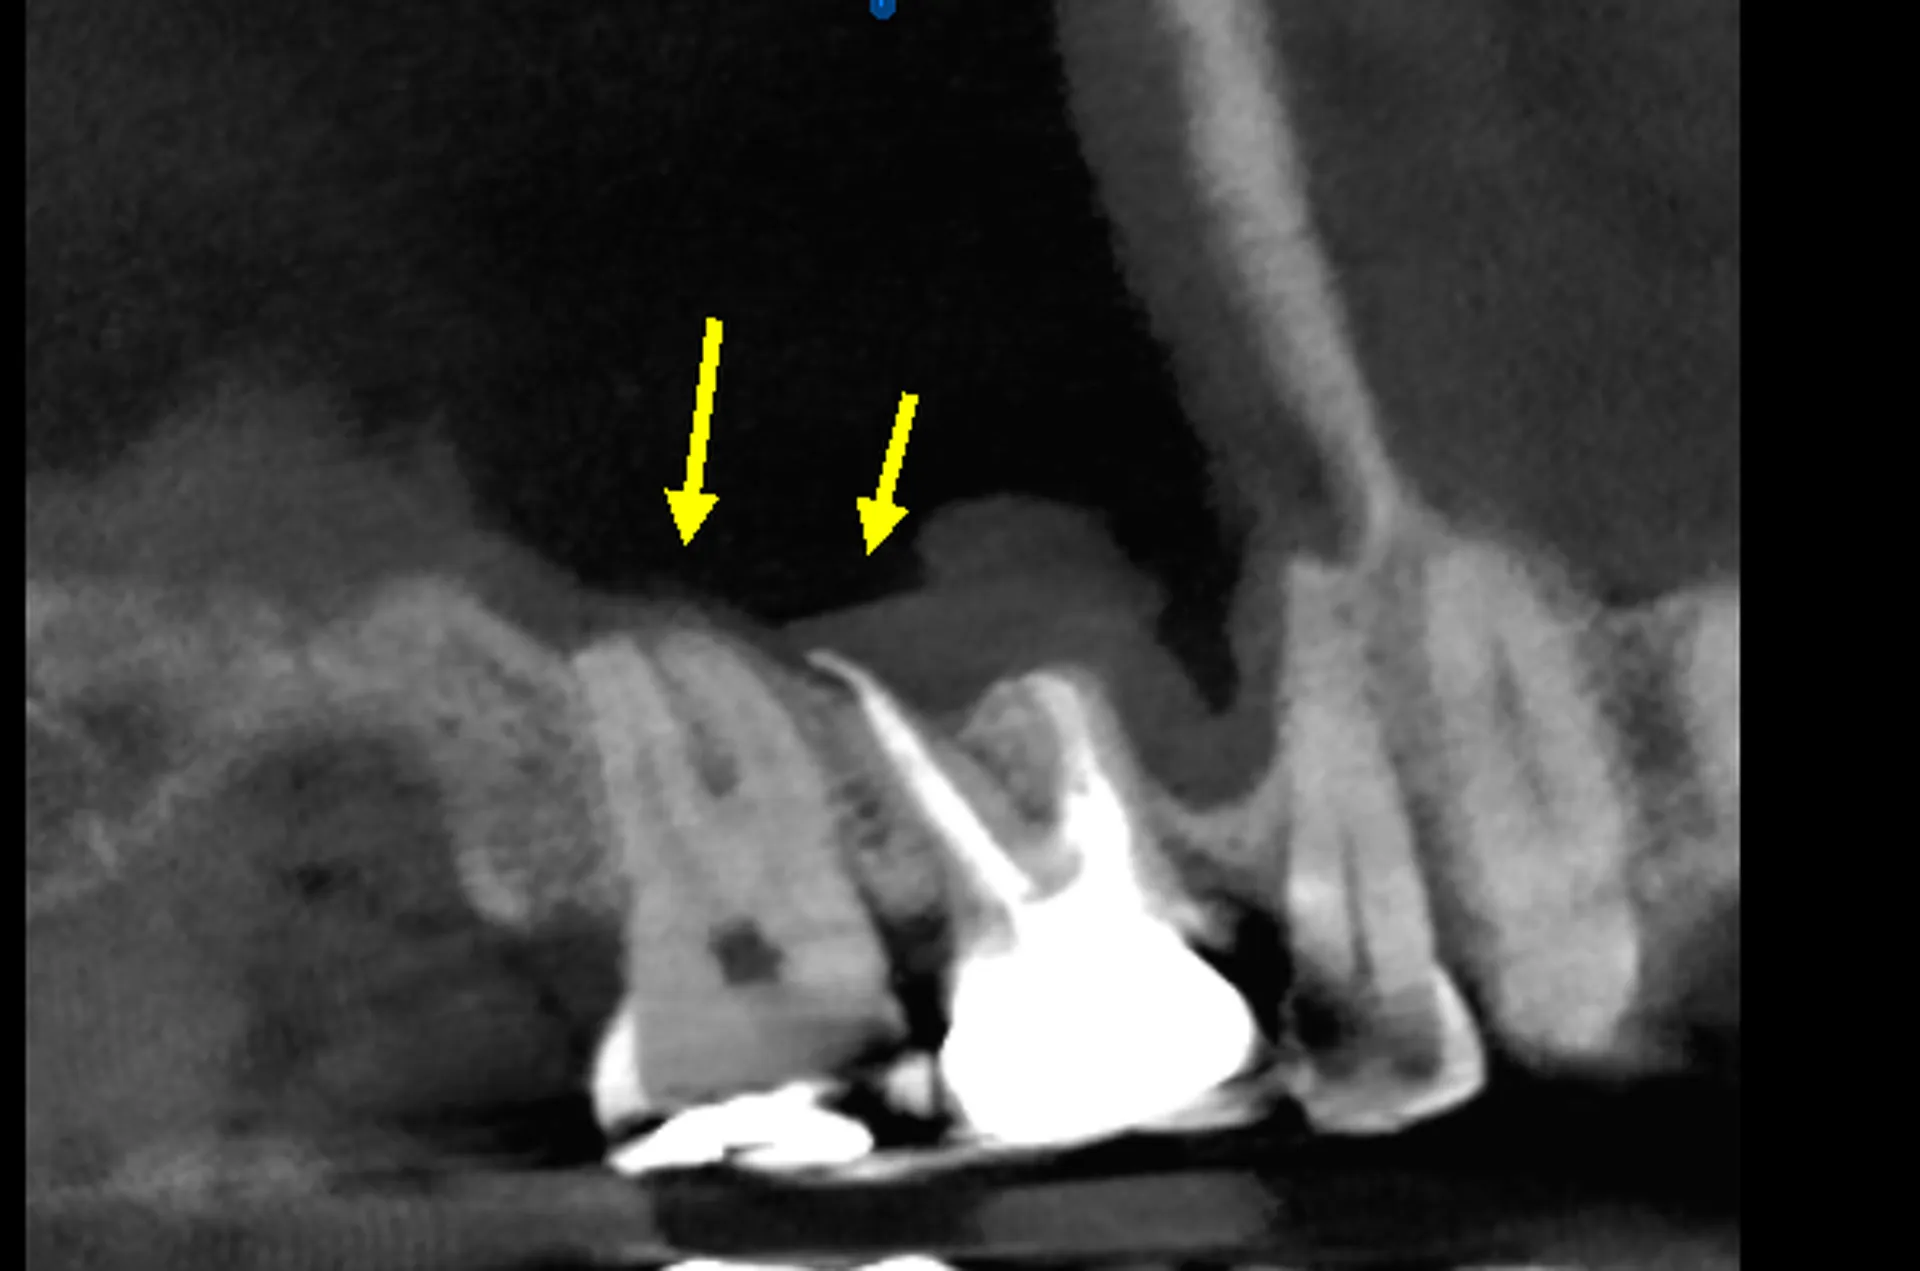

- Diagnosis: The process of diagnosis starts with a thorough examination of the teeth and gums by the dentist. X-rays may be taken to check the inside of the tooth and surrounding bone. Sometimes a 3D Cone beam CBCT scan may be necessary.